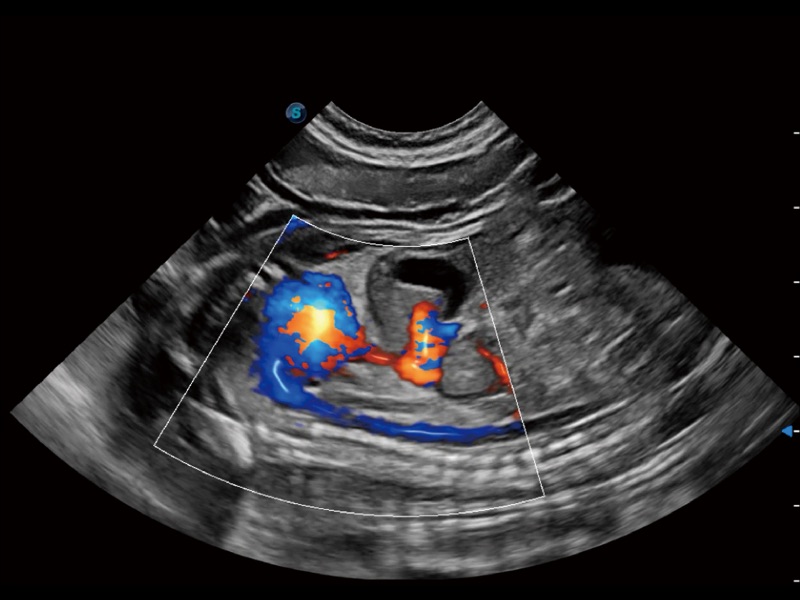

(犬)四腔心

(犬)四腔心MQA